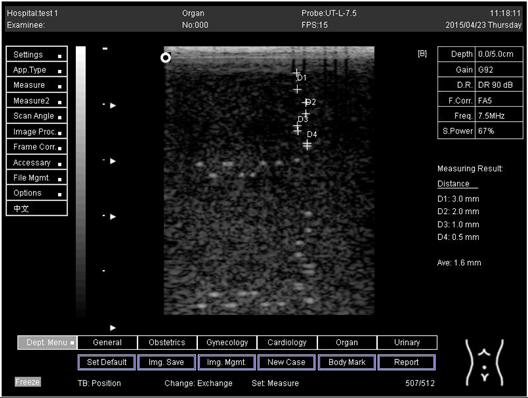

7.0 Axial resolution

Biomimetics 07 00130 i015

D1 = 3.0

D2 = 2.0

D3 = 1.0

D4 = 0.5

7.0Lateral resolution

Biomimetics 07 00130 i016